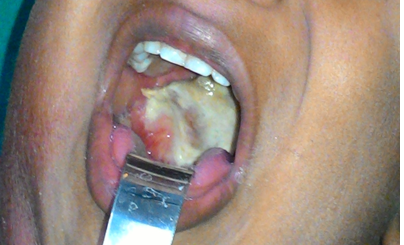

Czym są błony rzekome?

Powstają w miejscu wniknięcia C. diphteriae. Mlecznego koloru błony pokrywające gardło, migdałki, języczek. W nich znajdują się maczugowce błonicy produkujące egzotoksynę błoniczą.

Opisz objawy gardłowej postaci błonicy.

Błony rzekome